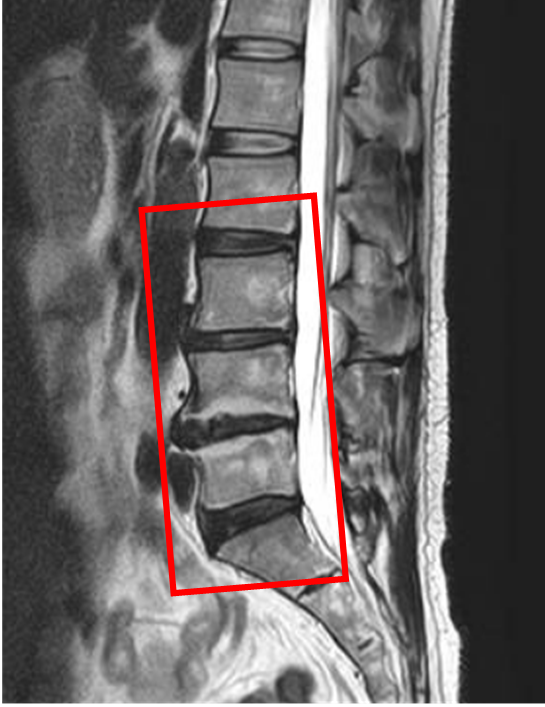

この患者様は赤い枠で示されている箇所(L2/3,3/4,4/5,5/s)に椎間板変性を認めます。